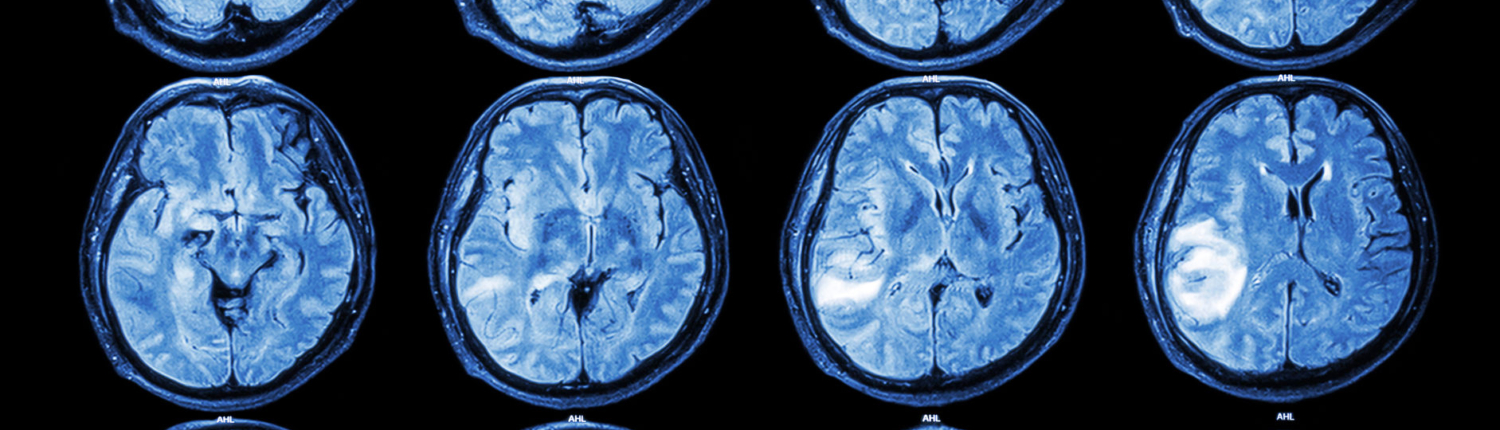

4. Brain Bleeds (Intracranial Hemorrhage)

Bleeding inside or around the brain can cause severe brain damage, coma, or death. Common types include subdural hematomas, epidural hematomas, and intracerebral hemorrhages.